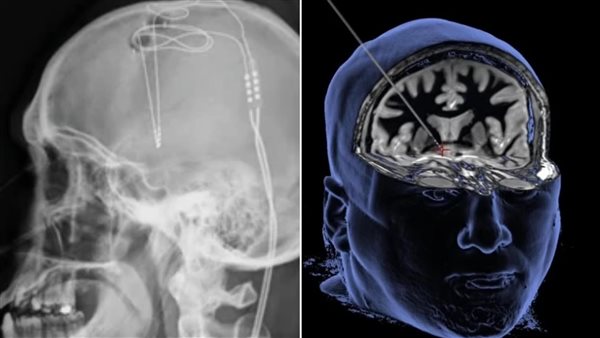

ووفقًا لما نشر في صحيفة ديلي ميل البريطانية، تقع هذه المنطقة التي تسمى النواة المتكئة، في منتصف الدماغ وعندما تصل الموجات فوق الصوتية إلى المنطقة، فإنها تتسبب في اهتزاز أغشية الخلايا وتعطيل نظام المكافأة الذي يعاني منه الناس مما يؤدي إلى الإدمان.

وتعد الطريقة الجديدة هي إجراء طبي معتمد من إدارة الأغذية والعقاقير، يتضمن إدخال أقطاب كهربائية صغيرة في فتحتين صغيرتين يتم حفرهما في الجمجمة وإدخالها في منطقة المكافأة في الدماغ.